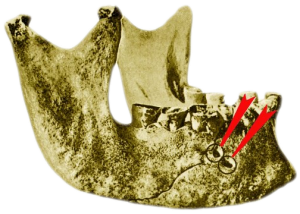

Визуальное и рентгенографического исследование нижней челюсти древнеегипетской мумии, проведённое в 1917 г., выявило два симметричных и параллельных трепанационных канала, начинающихся в кортикальной пластинке, чуть выше ментального отверстия нижней челюсти, и заканчивающихся у верхушки медиального корня первого моляра. Данный канал был просверлен первобытным бором для создания оттока из гнойного очага в области верхушки корня.

- Трепанация нижней челюсти

- Периодонтит

В лаборатории антропологии Музея человека в Париже находится экспонат с похожим клиническим случаем. Нижняя челюсть с двумя параллельными трепанационными отверстиями в области верхушки дистального корня 36 зуба.